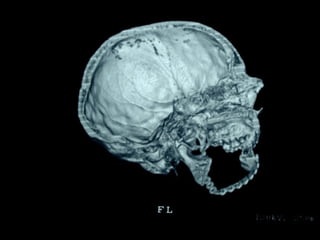

Esclerosis lateral amiotrófica Crouzón

Una enfermedad congénita es aquella que se manifiesta desde el nacimiento,

ya sea producida por un trastorno durante el desarrollo embrionario, durante el

parto, o como consecuencia de un defecto hereditario.